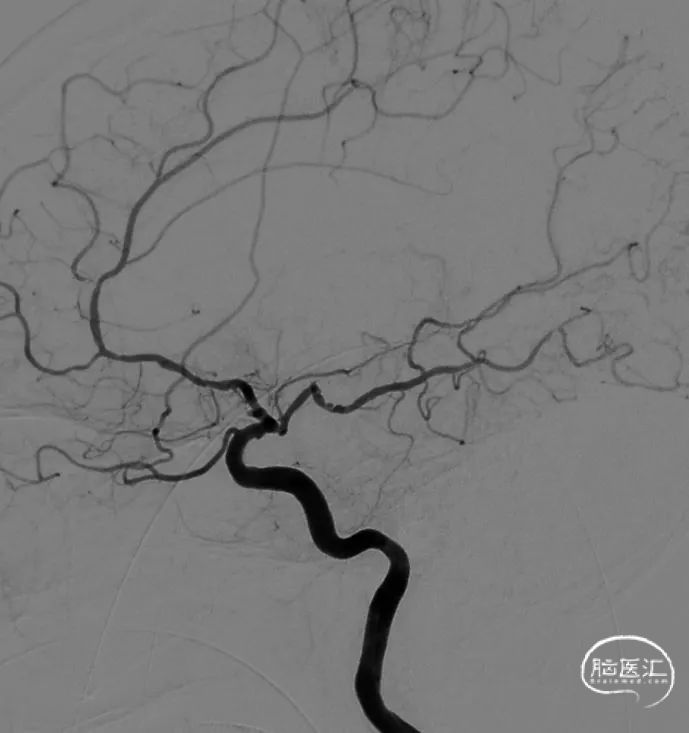

术中DSA

术后造影